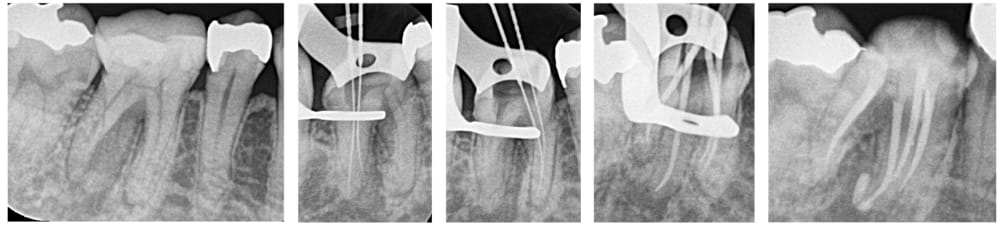

術前→ファイル試適→ガッタパーチャ試適→根管充填+コア築造後

湾曲が強い根管は、器具の破折を起こさないように慎重に処置を進めました。

4根管とも根尖まで穿通し、十分な細菌の除去を行ったのちに、根管充填を行い、レジンで封鎖し治療は完了しました。